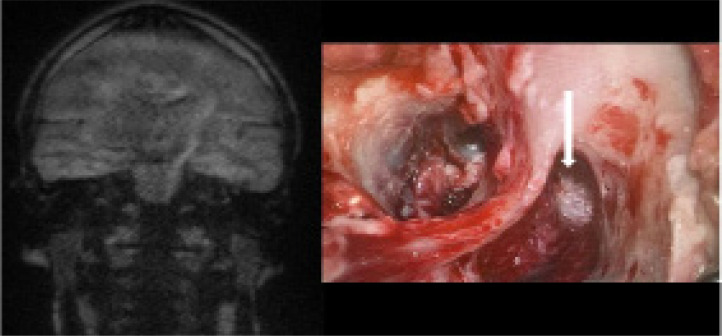

Results: Clinical and radiological concordance was found in 80% of patients. True positive results were observed in 77.5% of cases, while true negative results were noted in 2.5%. False positive results occurred in 8% of cases, mainly due to wax in the external auditory canal. False negative results were found in 12% of cases, often due to small or mural cholesteatomas. The sensitivity of MRI DWI non-EPI in detecting cholesteatoma was 87%.

Conclusions: MRI DWI non-EPI is an effective tool for detecting cholesteatoma recurrence, potentially avoiding unnecessary second-look surgeries. Awareness of false positive and negative results is crucial, and correlation of MRI findings with clinical examinations is recommended. To minimise false results, ear cleaning before MRI and repeated examinations at intervals are advised.